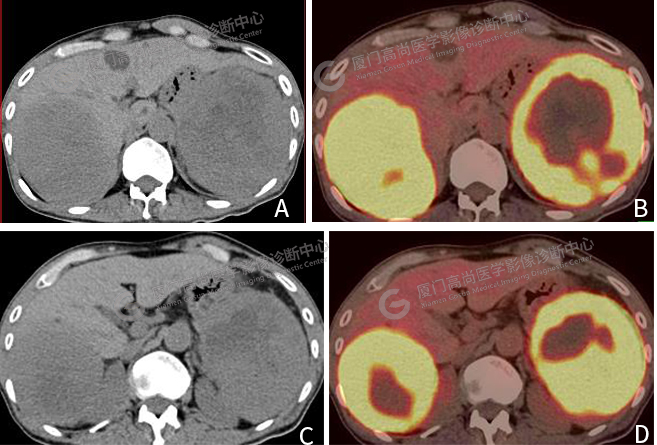

圖片圖3:A、 C CT圖像,肝臟右葉巨大腫塊影,脾臟內(nèi)巨大軟組織腫塊,代謝顯著增高。B、 D PET/CT融合圖像,腫塊代謝異常增高。

肝臟右葉見一巨大腫塊影,大小約10.0×8.6cm,F(xiàn)DG攝取明顯增高,SUVmax 16.1。脾臟內(nèi)見一巨大軟組織腫塊,大小約11.6×10.2cm,F(xiàn)DG攝取明顯增高,SUVmax 18.3(圖3)。

肝臟、脾臟轉(zhuǎn)移瘤呈多發(fā)性、結(jié)節(jié)狀,病灶中心密度較周邊低,“牛眼”征或“靶心”征為典型表現(xiàn)。此病例同時(shí)出現(xiàn)肝脾單發(fā)巨大轉(zhuǎn)移實(shí)屬罕見。